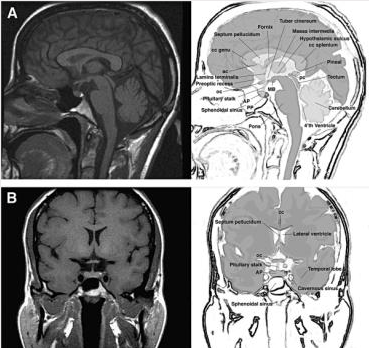

垂體瘤是一組從垂體前葉和后葉及顱咽管上皮殘余細(xì)胞發(fā)生的腫瘤。臨床上有明顯癥狀者約占顱內(nèi)腫瘤的10%。男性略多于女性,垂體瘤通常發(fā)生于青壯年時(shí)期,常常會(huì)影響患者的生長(zhǎng)發(fā)育、生育功能、學(xué)習(xí)和工作能力。臨床表現(xiàn)為激素分泌異常癥群、腫瘤壓迫垂體周圍組織的癥群、垂體卒中和其他垂體前葉功能減退表現(xiàn)。腫瘤好發(fā)于垂體前葉,后葉少見。多數(shù)為良性腺瘤,少數(shù)為腺癌。直徑小于10mm者為微小瘤,大于10mm者為者為大腺瘤。

垂體瘤手術(shù)的術(shù)中MRI

在紀(jì)念斯隆凱特林,我們的病人受益于使用術(shù)中磁共振成像輔助去除垂體腺瘤。

MRI是一種使用強(qiáng)磁場(chǎng)拍攝身體內(nèi)部照片的測(cè)試。術(shù)中MRI是指在手術(shù)過程中使用MRI掃描儀。

由MRI產(chǎn)生的圖片顯示正常組織和患病組織之間的差異。MRI掃描不涉及使用輻射。